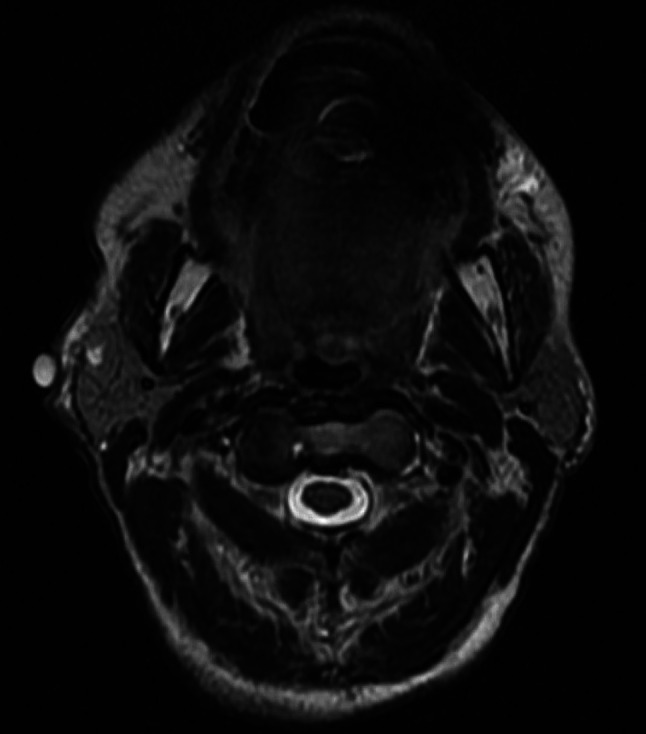

A 69-year old Caucasian female presented with a right parotid mass located at the angle of the mandible. MRI demonstrated a focal dilation of the right Stensen’s duct and a 2 mm nodule in the right superficial parotid suggestive for benign pleomorphic adenoma. (Fig. 1) On physical exam, the mass was palpable and approximately 0.5 cm. Subsequent fine needle aspiration demonstrated “cohesive groups of epithelioid cells and abundant chondroid matrix like material,” and could not rule out pleomorphic adenoma.

Fig. 1.

Axial view of T2-weighted images of MRI face that demonstrates high intensity of a small right parotid mass